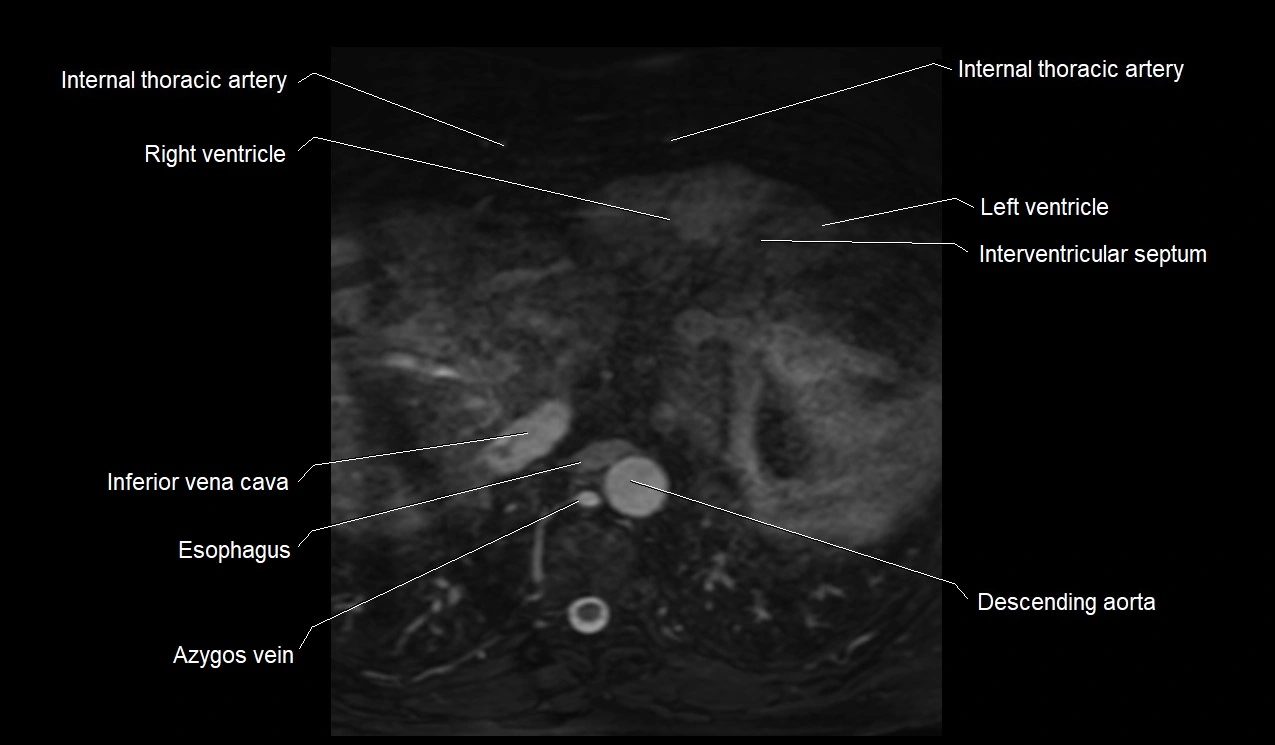

MRI image